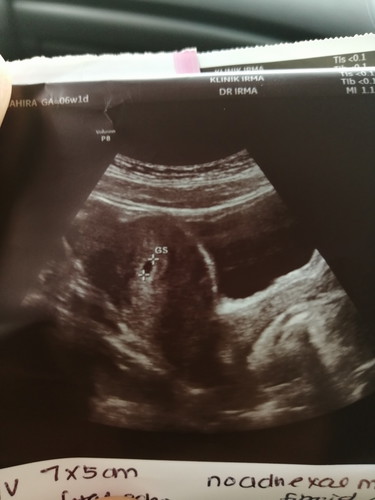

Brown Spotting

Hi semua, nak tanya. Saya baru kahwin awal tahun ni. Dan last period saya masa bulan puasa. saya check UPT positif and doc scan baru nampak kantung je. Ikutkan saya dah 7 weeks. Tapi semalam saya perasan ada keluar cecair period tetapi warna coklat. Sekali je and kemudian dah stop. Adakah itu normal? Sebab ada baca banyak article, so takut juga ?